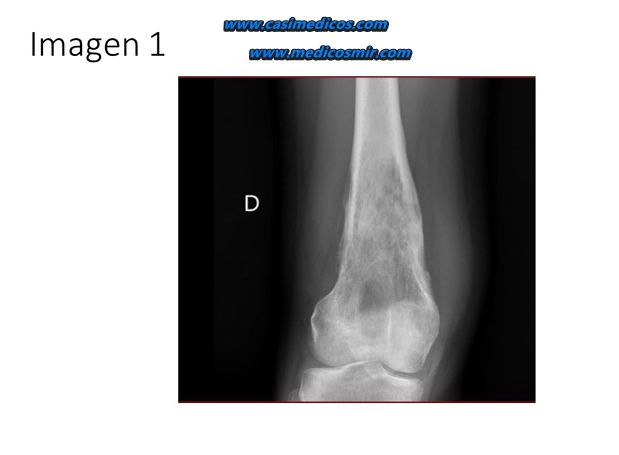

En un adolescente de 17 años con dolor de rodilla de tres meses de evolución, antecedente de traumatismo leve y esta radiografía, ¿cuál de las siguientes entidades debe considerarse en el diagnóstico diferencial según la clínica y la imagen radiográfica (IMAGEN 1)?

Comentario: Radiografía de rodilla que muestra una lesión metafisaria agresiva con patrón mixto lítico-esclerótico y reacción perióstica, sugestiva de tumor óseo primario maligno, en cuyo diagnóstico diferencial debe incluirse el osteosarcoma.